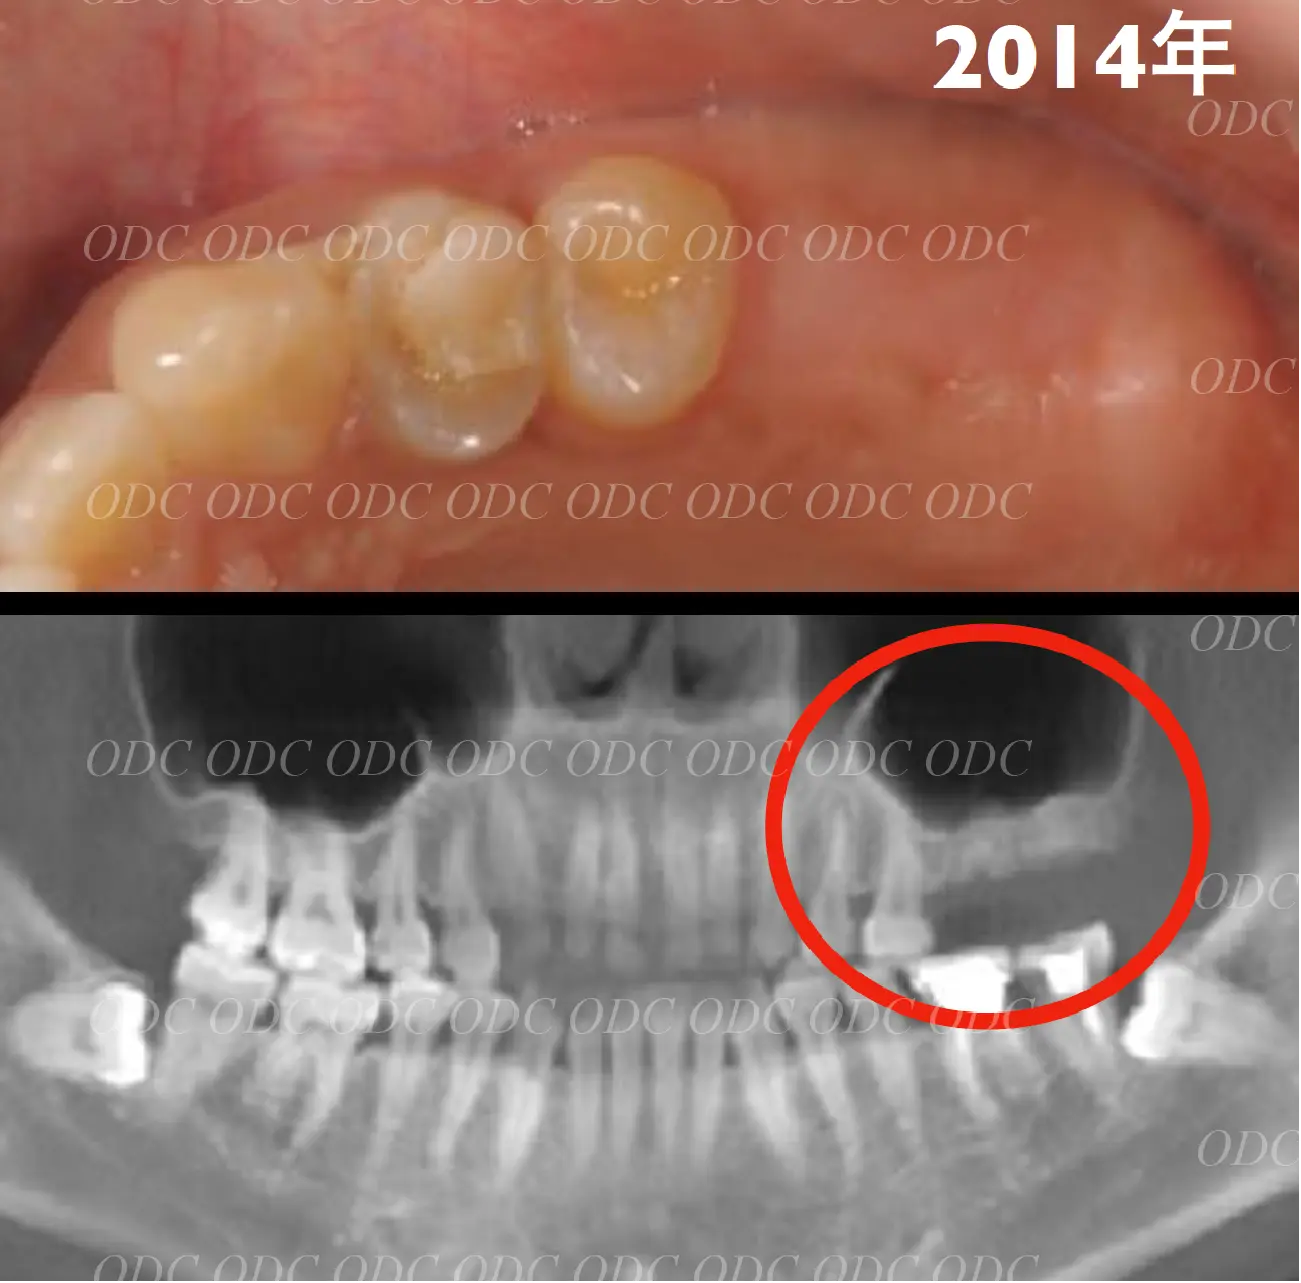

2011年、噛めないという主訴で65歳の男性が来院されました。

全顎的な治療を希望されていましたので、口腔内はもちろん骨格・顔貌・顎関節の診断を行い治療目標を設定致しました。

上顎天然歯に関しては矯正治療、下顎にはフルマウスのインプラント治療を計画致しました。

顎関節の安定を確認した後、矯正治療とインプラント治療を並行して行いました。

約3年の治療期間を経て、計画通りの満足のいく結果を獲得することができました。

2014年、治療終了時の口腔内の状態です。

インプラント上部構造はCADCAMによって作成されたジルコニアの上部構造です。

2024年、治療終了後約10年が経過いたしました。

顎関節を考慮した包括的な治療を行うことで咬合状態(噛み合わせ)は現在もとても安定した状態です。